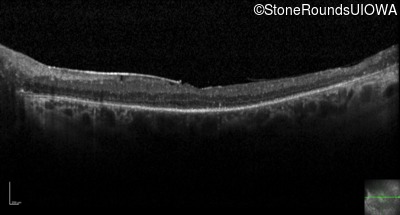

Optical Coherence Tomography - Left - 20/30 +2

Exemplar / OCT Stack